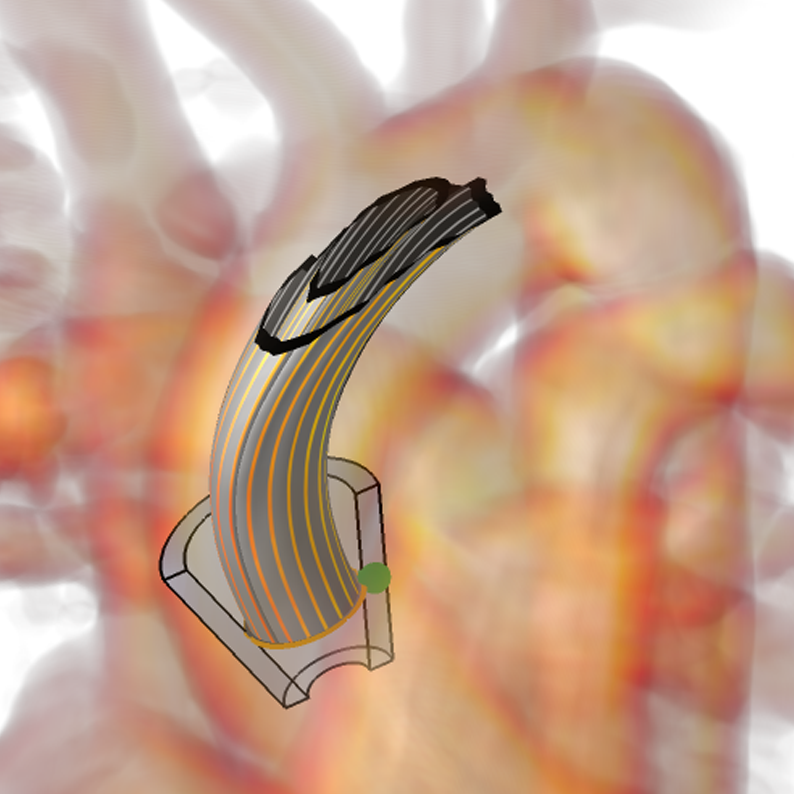

In later work, Van Pelt et al Pelt:2011a presented a probing technique to allow fast qualitative inspection, avoiding full segmentation. The user positions a 3D virtual probe on the viewing plane with common 2D interaction metaphors. An automatic fitting of the probe is provided for the third dimension, i.e., the viewing direction. Using the available velocity information of the measured blood flow field, the probe is aligned to this field. In particular, the automated fitting aligns the orientation of the long axis of the virtual probe to be tangential to the average local blood flow orientation. The probe is the basis for further visualizations (see Figure 9).